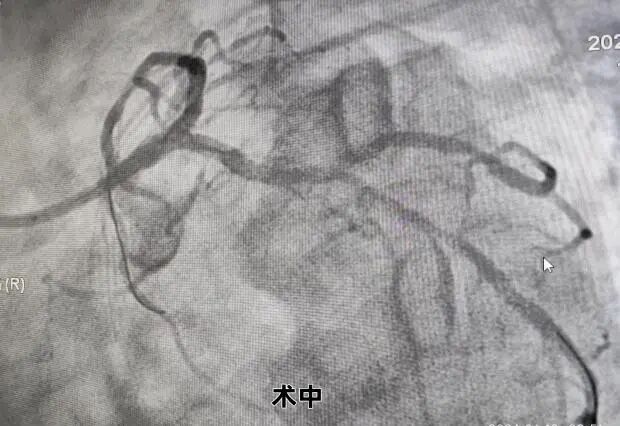

患者手术中

面对如此复杂高危的冠脉病变,制定合理的治疗策略非常关键,患者造影结束安返病房。随后在中组部“组团式”帮扶专家游琼主任医师指导下,徐宗荣及杨力副主任医师介入团队逐帧仔细判读冠脉造影结果,再次熟悉临床资料,认为该患者SYNTAX评分34分,遂建议首选外科搭桥手术,但患者与家属不同意外科手术并要求介入治疗。基于患者病情危重,病变复杂,介入手术难度极大,手术风险极高,需强支撑大管腔指引导管处理,介入团队综合考虑了患者病情及经济因素后,获得患者及其家属知情同意,决定迎难而上,经我院介入团队充分讨论及评估,利用桡动脉无鞘技术,采用IABP保护下采用SKS术式,成功植入4枚支架,手术总共耗时2个多小时,整个手术过程顺利,术中无并发症,患者术后恢复良好,胸闷痛基本缓解,目前患者已康复出院。